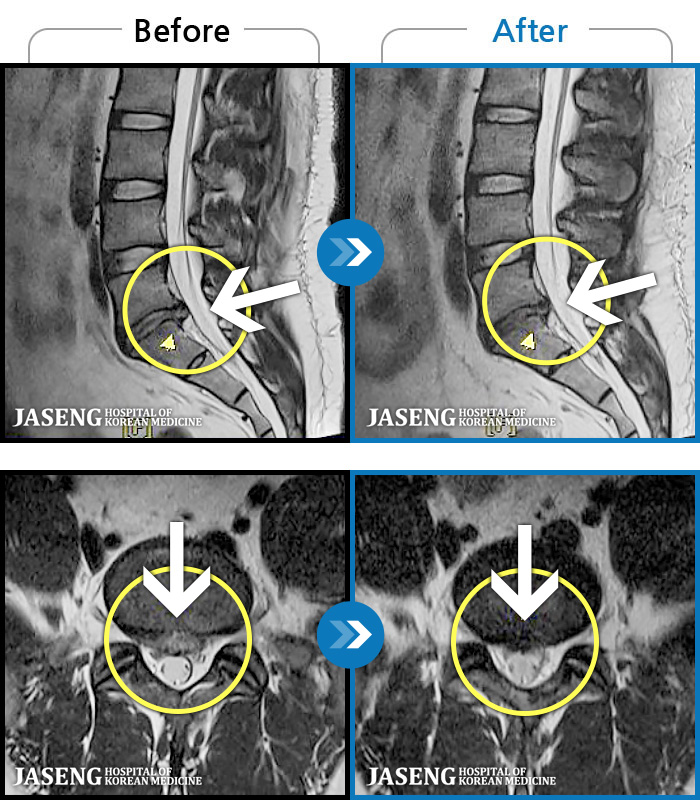

[뱸] 19.11.28~25.05.06

ȯںп Ǹ ǿ ԿǾ, ο ġ ۿ Ƿ ġḦ Ͻñ ٶϴ.